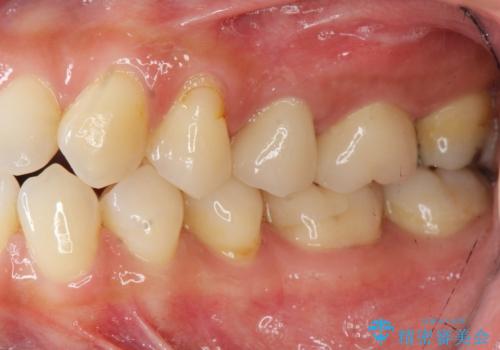

放置し崩壊した歯 セラミック治療による咬合機能回復

虫歯を丁寧に除去したのち、なんとか歯を残せる見通しがたったので根管治療を行いセラミック補綴を行いました。

- 24万円(仮歯×2・ファイバーコア・ジルコニアクラウン×2)費用は治療当時の料金となります

今回は歯を残すことができましたが、早期の治療が歯の長い予後の期待値をあげます。